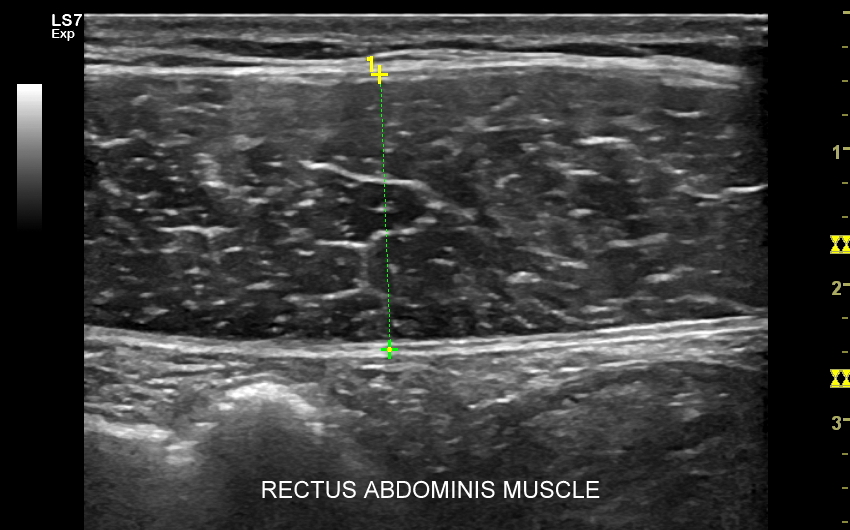

Badanie USG w obrębie uda najczęściej wykorzystywane jest przy diagnostyce urazów sportowych, wśród których dominują naderwania mięśni. Naderwania u dorosłych lokalizują się zwykle w okolicy przyczepu bliższego mięśnia czworogłowego uda, przyczepów bliższych i dalszych tylnej grupy mięśniowej (mięśnie półbłoniasty, półścięgnisty, dwugłowy uda) określanej zbiorczo z języka angielskiego jako hamstringi, a także w obrębie mięśni przywodzicieli. W mięśniach uda nierzadko u młodych dorosłych pojawiają się nowotwory mięsaki. U dorastających dzieci naderwania w zakresie jednostek ruchowych występują na przyczepach ścięgnisto-chrzęstnych lub chrzęstno-kostnych.